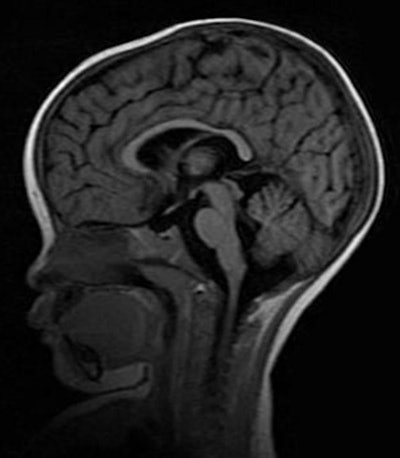

MRI shows normal brain volume in a 14-month-old girl at one-month follow-up. Images courtesy of Michigan State University and GE Healthcare.More importantly, the first piece of critical evidence came from one of the first patients scanned on the newly donated MRI. The child came to the hospital with typical cerebral malaria symptoms, including retinopathy. The comatose patient had an MRI on day 1 and a second one on day 2, but died four hours after the second scan.

MR image shows increased brain volume in a 19-month-old girl with retinopathy-positive cerebral malaria.Because of the pressure on the foramen magnum, the retinopathy-positive patients with cerebral malaria inevitably died because they stopped breathing.